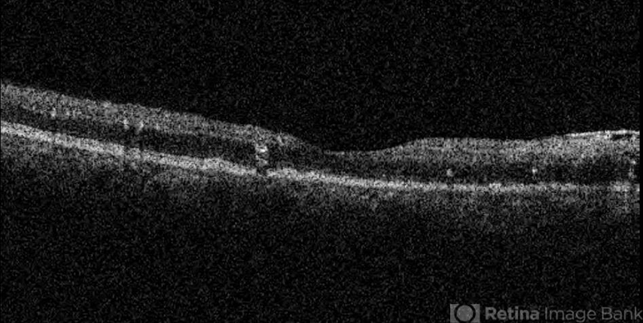

- primary hyperoxaluria, oxalosis, optical coherence tomography (OCT)

- OCT image of the right eye of a 55- year- old woman with primary hyperoxaluria and oxalosis. Intraretinal and sub- retinal deposition of calcium oxalate crystals are visible .